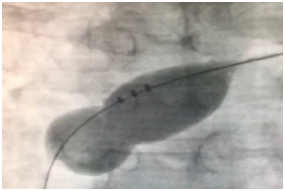

The Amplatzer Septal Occluder (ASO) is now one of the most widely used devices for trans-catheter closure of ASD. Although the ASO resolved some potential limitations of previous methods such as the non-negligible rate of residual shunt and frame fracture, it may still lead to severe cardiac adverse events in about 0.2% of patients mainly due to oversizing the device due to the size of the defect and aortic rim deficiency.9 ASD sizing is usually based on the TEE that will evaluate the size and rims. Although before closure in the catheterization lab, the uses of the sizing balloon will help and, based on the waste will measure the ASD size and estimate the appropriate device size (Figures 2). The initial study revealed a failure rate of 4.3% with significant and total adverse effects of 1.6% and 7.2%, respectively.10 By developing the third generation of occluders like the Figulla Flex II ASD occluder, the risk for cardiac erosion has been significantly reduced. Some large studies demonstrated high efficacy with low complication rate (<1%)when Figulla Flex II ASD occluder is used.10  However, in some other studies, comparable efficacy and safety were shown compared to ASO.11,12 Because of the contradictory results regarding the consequences of the use of Figulla Flex II ASD occluder as a new generation of ASD repair technique, we evaluated the long-term efficacy of using this device in a tertiary referral heart center to find a more unobstructed view of the values about this new device.

Figure 2 Sizing Balloon during the procedure of ASD closure.